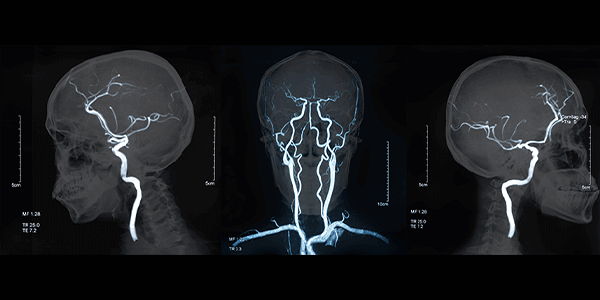

Cerebral angiography is a minimally invasive medical imaging method used to visualize the blood vessels in the brain. This technique is used to detect narrowing, blockages, aneurysms, and other abnormalities in the brain’s blood vessels. Cerebral angiography plays an important role in the diagnosis and treatment of neurological diseases.

Cerebral angiography is an imaging method used to obtain images of the blood vessels in the brain. In this procedure, a thin catheter (plastic tube) is inserted into an artery, such as the femoral artery in the groin or the radial artery in the arm, and guided to the brain’s blood vessels under X-ray imaging. Contrast material is injected into the vessels through the catheter, and X-ray images are taken. These images provide detailed information about the structure and blood flow of the brain’s vessels.

• MR Angiography: An angiography performed using magnetic resonance imaging (MRI). It can be done without contrast material or with a reduced amount of contrast.